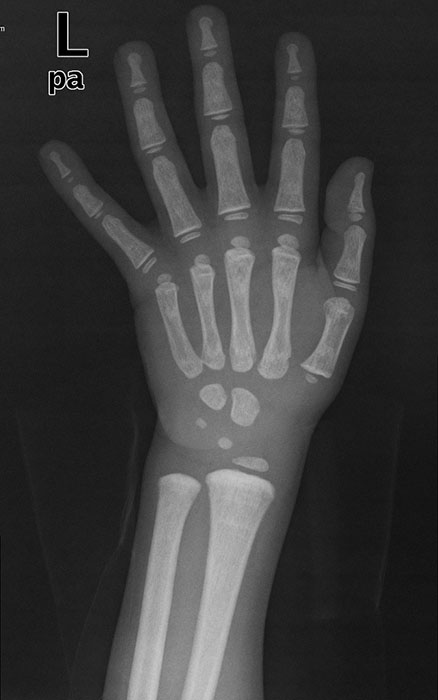

<p>This patient is 5 years old. What pathology do the have.</p>

This patient is 5 years old. What pathology do the have.

Advanced bone age (look at carpals)